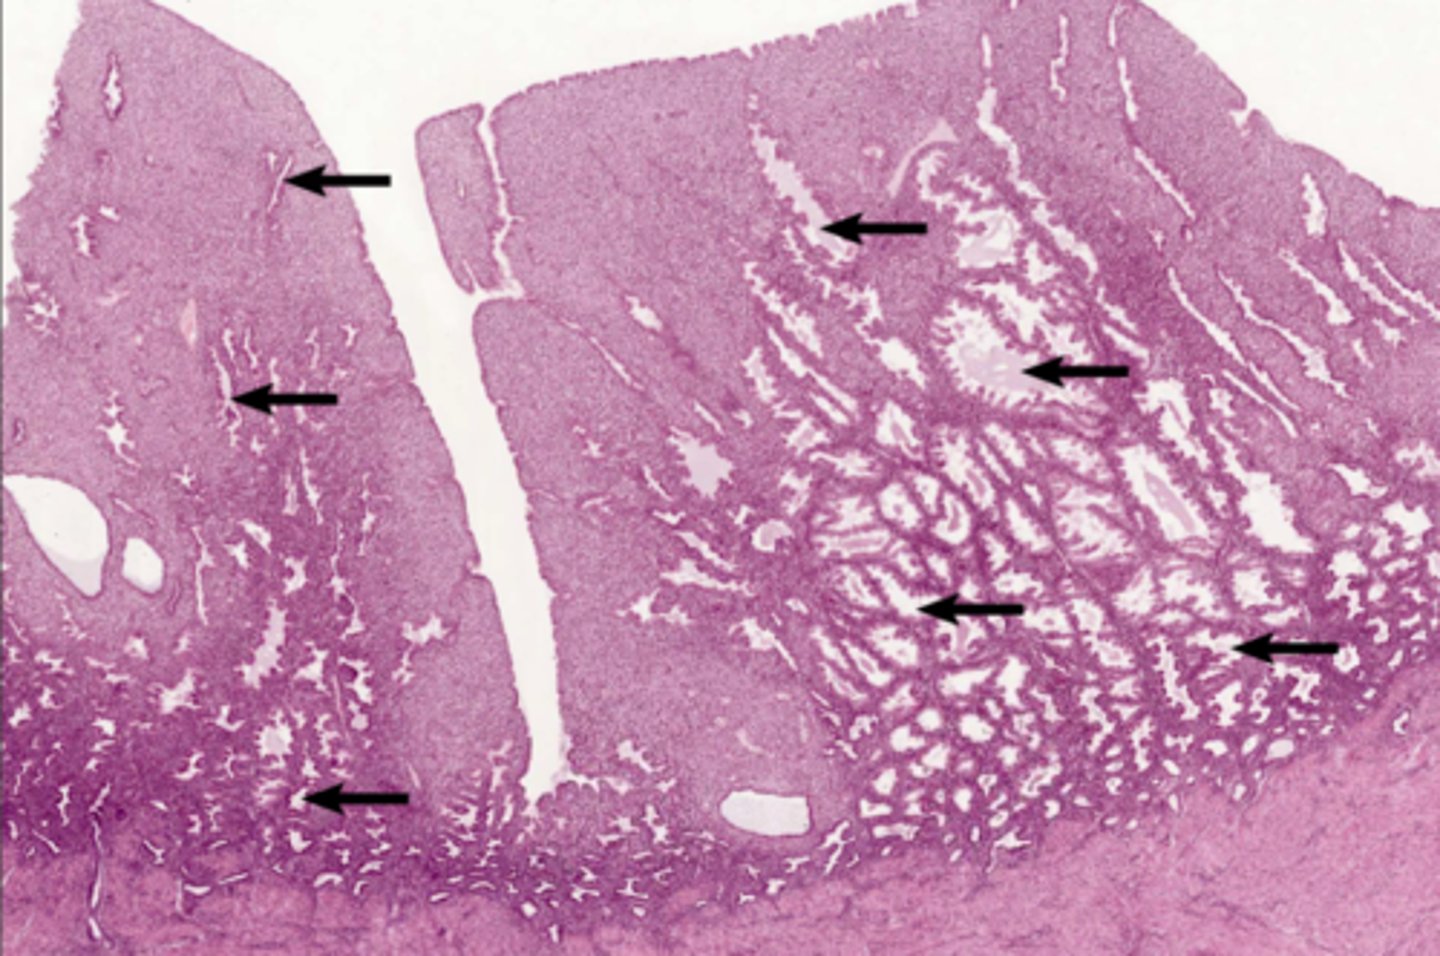

Endometrium

Endometrium

proliferate functional layer

secretory functional layer

menstrual functional layer

proliferate basal layer

secretory basal layer

menstrual basal layer

Uterine gland